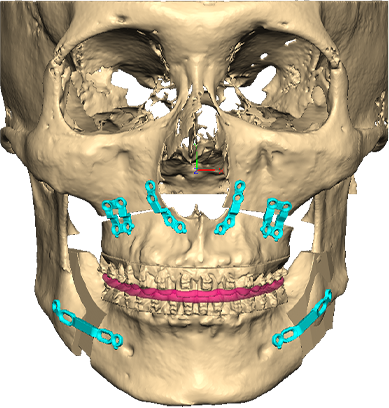

3D플랜에 따라 최적의 위치로 상-하악을 위치시킴

무턱 교정을 위해 하악을 앞으로 이동시켜 적정한 교합을 맞춤

플랜을 기반으로 제작된 Wafer를 장착하고 뼈를 고정

무턱 개선 : 턱 끝 기준 14mm 전진

Wafer를 이용해 상악의 돌출을 뒤로 교정 무턱의 하악을 앞으로 빼내어 정상교합에 위치시킨 뒤, 맞춤형 Plate로 뼈를 고정

무턱 개선 : 턱 끝 기준 17mm 전진